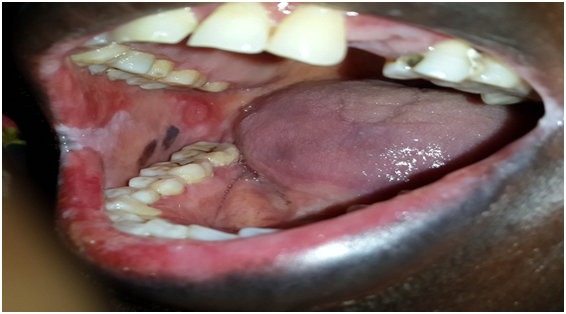

Clinical examinations: Tender diffuse irregular shallow bloody ulcers affected the lower lip and bilateral buccal mucosa and oral commissures. Also bilaterally a racial pigementations were appeared on buccal mucosa (Figures 1-3). There were no detectable cutaneous target like lesions and no palpable submandibular or cervical lymphadenopathy.

Figure 3 Shows diffuse irregular bloody ulcerations in the labial mucosa and in corner of the mouth.